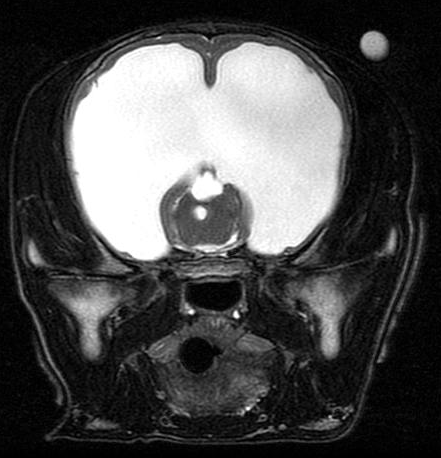

A ressonância magnética em cachorro é um dos exames mais avançados da medicina veterinária moderna. Indicada principalmente para avaliação do sistema nervoso, articulações e tecidos moles, ela permite diagnósticos precisos que muitas vezes não são possíveis com exames convencionais.

A ressonância magnética é uma das ferramentas mais avançadas para diagnóstico por imagem, permitindo visualizar estruturas internas com alta precisão e sem procedimentos invasivos. Em pets, esse exame é essencial para identificar alterações neurológicas, ortopédicas e de órgãos internos com segurança e rapidez.